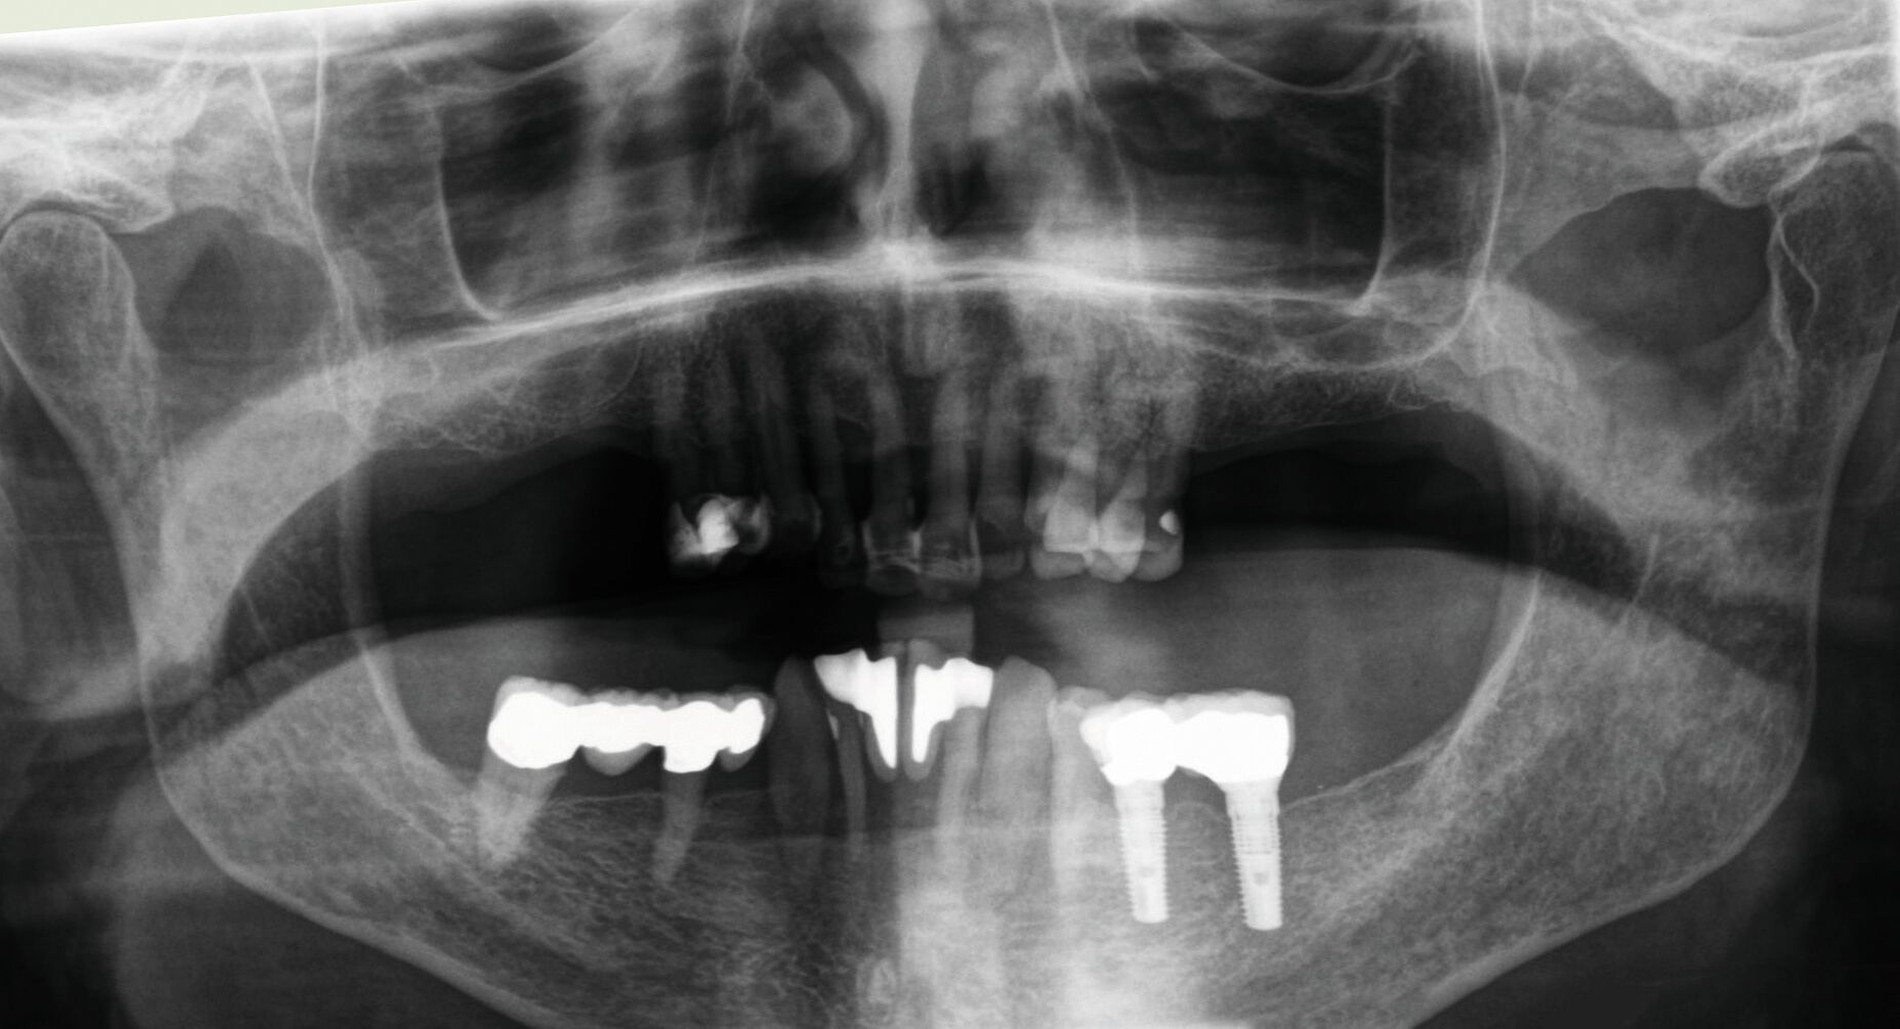

Danach wurde der Klinikbesuch für den inzwischen 83-Jährigen zu beschwerlich, und er wurde von einem wohnortnahen Zahnarzt betreut. Die von ihm 19 Jahre nach Eingliederung des Zahnersatzes angefertigte Panoramaschichtaufnahme dokumentiert die unveränderte prothetische Versorgung des Unterkiefers sowie die stabile Situation der verkürzten Zahnreihe im Oberkiefer (Abbildung 16). Für eine detaillierte Darstellung des Fallberichts wird auf die Originalpublikation verwiesen [Wolfart und Kern, 2024].